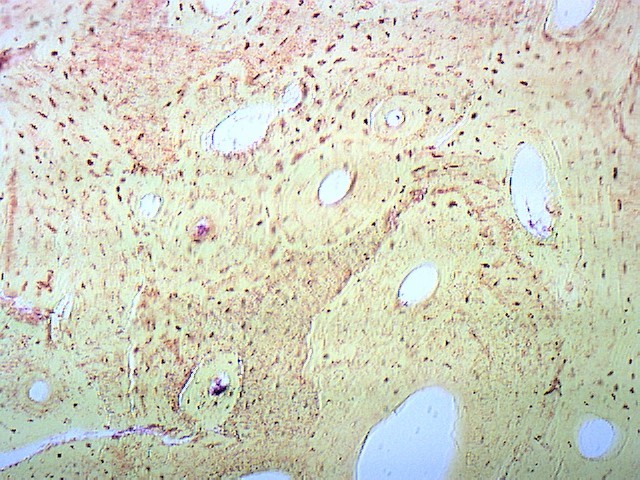

Костная ткань - 3 шт.